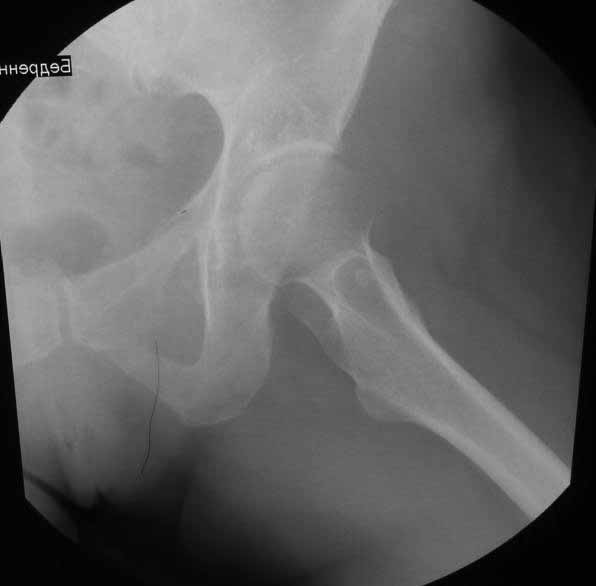

Стрессовый перелом лонной кости и нестабильный эндопротез с противоположной стороны. |

Уважаемые коллеги. Хотелось бы услышать мнения и советы по представляемому случаю. Пациентка 45 лет. Бесцементное эндопротезирование левого тазобедренного сустава 6 лет назад (впадина RM, Mathys, металл-металл, ножка Зульцеровская). За 10 лет до протезирования – коррегирующая остеотомия бедренной кости, которая не срослась в течение года до удаления пластины, а затем срослась в течение 3 месяцев иммобилизации в кокситной повязке. После протезирования получилось наблюдать пациентку почти постоянно, поскольку через 2 года синтезировал ей лодыжки на оперированной стороне, затем, через несколько месяцев удалил фиксаторы, а в 2009г. резецировал мениск на противоположной стороне. Боли все эти годы не беспокоили. Пациентка чуть выше среднего роста, вес тела нормальный. Физические нагрузки переносила хорошо. Работает на 7 этаже без лифта. Год назад экстирпация матки по поводу лейомиомы больших размеров. Несколько месяцев назад появились боли в области левого тазобедренного сустава. При рентгеновском и КТ исследованиях (июль с.г.) – нестабильность тазового компонента. От предложенной замены протеза пациентка на тот момент, слава богу, отказалась. Через какое то время боли в области левого тазобедренного сустава практически полностью прошли, а около 2 месяцев назад появилось ощущение патологической подвижности таза и боли в паху справа, которые через некоторое время уменьшились, а потом снова усилились после значительных физических нагрузок (много ходила по песку на пляже, носила тяжести). Ежедневно принимала диклофенак. На рентгенограммах – переломы правой лонной кости. Сейчас госпитализирована из-за болей в паху справа. Боли слева не беспокоят. На фоне снижения нагрузок в стационаре боли значимо уменьшились. Способна ходить без средств дополнительной опоры.В анализах крови чуть повышены трансаминазы и гамма-ГТ, моча без особенностей.

Вопросы: -правильно ли я расцениваю переломы как стрессовые на фоне неполноценного таза (pelvic insufficiency stress fractures)? -Можно ли так же расценить ситуацию на стороне протеза и, соответственно, не торопиться с ревизией, рассчитывая на вторичную стабилизацию? Уж больно не хочется менять ножку. -Если думать о ревизии, то когда? На представленных снимках тазобедренный сустав до и сразу после операции, затем 2 снимка 2009г., когда ничего не беспокоило, затем КТ 2-х месячной давности и вчерашние рентгенограммы обоих тазобедренных суставов.

Если внимательно посмотреть на рентгеновские снимки, то видно, что пара трения действительно металл-металл.